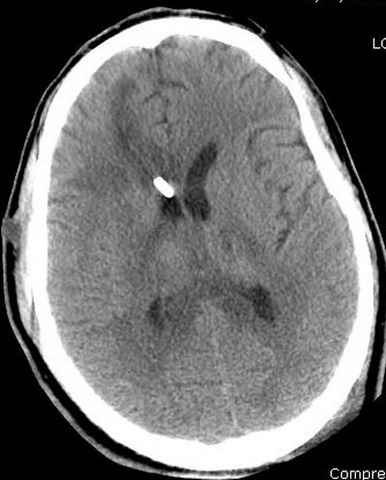

больному 42, автоавария, политравма, открытая черепномозговая травма, безсознании, открытый перелом бедра, размозжение мягких тканей, дефект кожи на передней поверхности бедра около 13 см2 от ожога, компартмент синдром.

Наблюдается службой травмы и нейрохирургии (ICP) Increased Intracranial Pressure by ventricular cateter

больной без сознания, со слов нейрохирурга, наблюдается положительная динамика в нейрохирургическом статусе.

-Согласен, рана до прихода пластического хирурга была 38х13 см, можно было постараться закрыть сверху, а в нижнем отделе где был ожог, применить кожную пластику меньшим размером. К моему удивлению и разочарованию, когда вернулся из другой операционной (шли пареллельные операции), он уже успешно заканчивал свое дело. Кстати недавно разговаривал с нейрохирургом, он снял ICP (intracranial prеssure monitor), внутричерепное давление стабилизировалось, ортопеды и хирурги закончили с лечением, теперь длительное неврологическое восстановление.